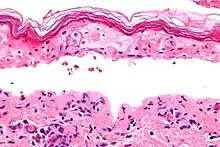

| Micrograph of confluent epidermal necrosis. H&E stain. | |

Erythema multiforme major is a form of rash with skin loss or epidermal detachment.